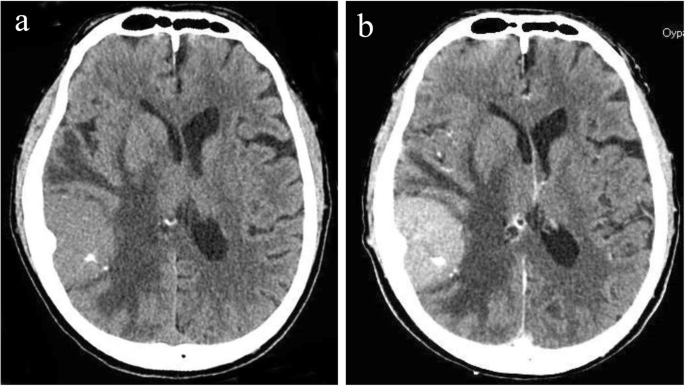

We stopped the dialysis session and performed head CT. It showed a brain tumor of 5 cm with diffuse cerebral edema (Fig. 1). Additional enhanced CT for tumor scrutiny resulted in a diagnosis of meningioma morphologically. The cerebral edema had been exacerbated by dialysis, inducing convulsions when the brain pressure had been increased due to occult meningioma.

Of note, we did not perform close scrutiny in this case when cloudy consciousness was first noted after the initial dialysis session. Since this patient started emergency dialysis with numerous factors associated with a risk of DDS, we did not vigorously search for other causes when neurological abnormal findings appeared. Regarding the subsequent course of this case, 1 week after the onset of convulsions and consciousness disturbance, his consciousness became clear. However, the midline shift remained even 2 weeks later, although the cerebral edema had been alleviated, and the improvement on CT images was considered insufficient. The midline shift finally disappeared after about a month, and the cerebral edema improved on CT, being localized only around the tumor. After 1 month, no further improvements on images were noted (Fig. 3).

Temporal changes on the image in abnormal cerebral edema and midline shift. Head CT scan on day 28 revealed improvement in midline shift. FLAIR image that was performed on day 67 showed marked improvement in brain edema around tumor on the right temporal region. FLAIR fluid-attenuated inversion recovery